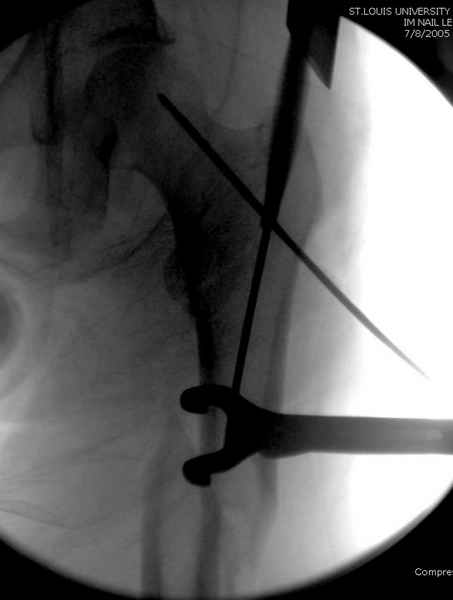

Как раз недавно у меня был примерный случай: больному 36 лет, поступил ночью, травма в результате мотоциклетной аварии, кроме чрезвертельного и спирального перелома левого бедра имеется переломы костей предплечья с этой же стороны. Скелетное вытяжение, а на следующий день больной про оперирован на ортопедическом столе с дистракцией. Чтобы не расколоть чрезвертельный перелом провели временную спицу ближе к переднему кортексу, из малого разреза костодержатель для репозиции, а фиксацию провели антиградным штифтом. Этапы операции на снимках.

Джолдас Кульджанов

DK> фиксацию провели антеградным штифтом.

Да, сейчас это и у нас самый напрашивающийся выбор. Сделали гвоздем ChM, картинки в приложении.